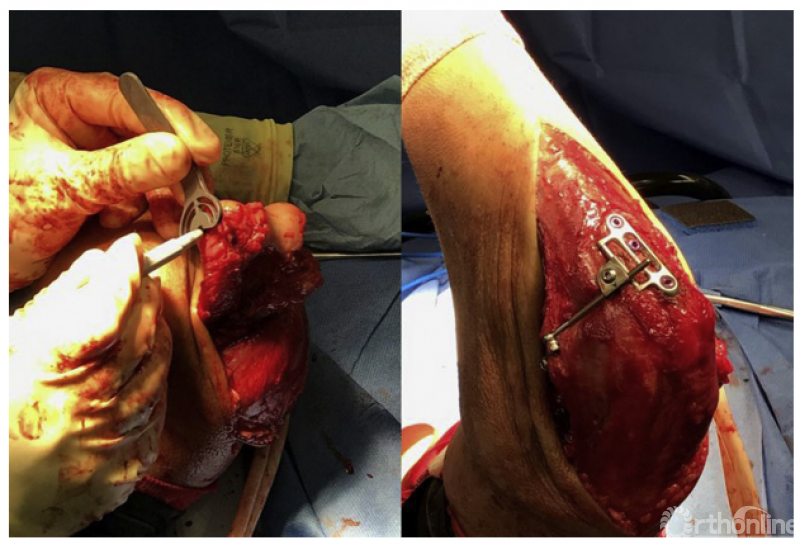

3、难以手术重建的冠状突骨折以及冠状突缺损导致的陈旧肘关节不稳定,既往有髂骨、鹰嘴、桡骨头、肋骨、异体骨等,甚至还有冠状突假体。Wegmann等通过三维空间影像学测量和配准,发现采用健侧鹰嘴尖50°截骨的骨块,和原始冠状突的形态最贴合,尤其是关节面部分,这也为今后重建冠状突提供了一种可行的解决方案。

1、肘关节旋转轴三维定位

国内蒋协远教授团队在世界上率先采用三维导航机器人进行肘关节旋转中心定位。TiRobot机器人导航辅助肘关节旋转中心轴定位能够极大地降低主观判断造成的旋转轴偏移,提高轴心定位精准度,减少反复透视验证的过度辐射及反复调整轴心导针的骨质破坏,避免可能的血管、神经损伤,显著减小降低术后肘关节活动阻力,并减少外固定针松动、断裂及外固定架断裂等并发症的发生率,从而整体提高治疗效果。